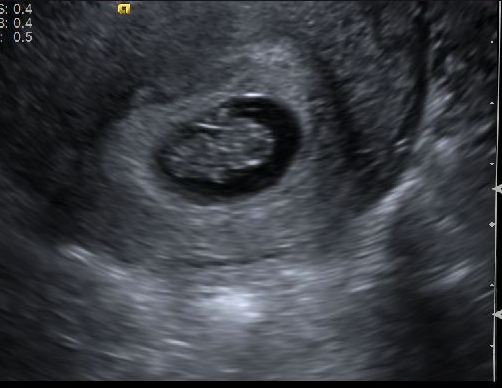

For good measure, here's an u/s pic. I was 8w2d yesterday.

I called and talked to a nurse yesterday morning, and she scheduled an u/s for the afternoon. I ended up going to the radiology department in the building, not to my OB's office, so the tech didn't give me much information, but she did show us the baby and heartbeat which was a relief. I don't know how much the baby has grown since my last u/s, but it definitely looks different than it did last time, so I'm assuming there's been a decent amount of growth. I'm pissed, though, because my doctor never called me with the u/s results yesterday, so I have to wait until Monday to see what she thinks might have caused the bleeding.